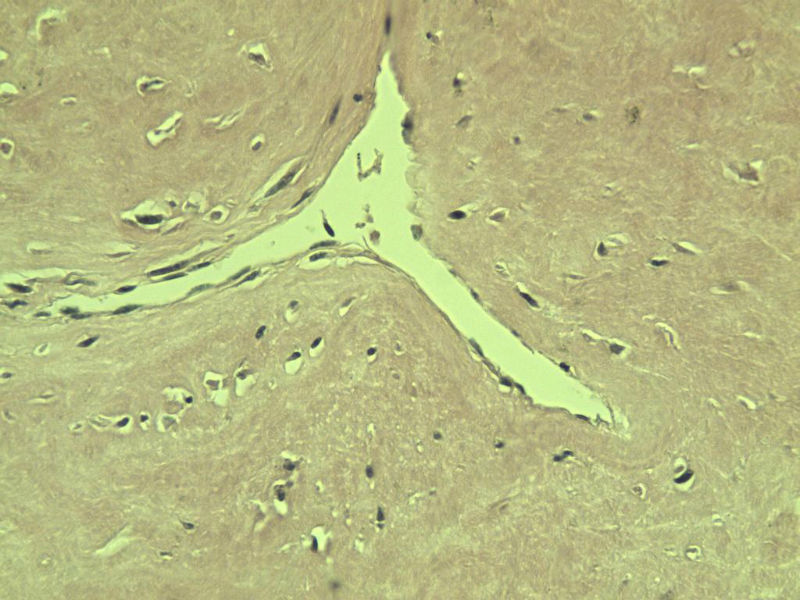

男,51岁, 4月前患者无意中发现右腘窝一包块,约核仁大小无疼痛, 4月来包块进行性生长

灰褐类圆形包块一个,直径 5 cm,切面灰白,实性,编织状。 请各位老师看看 是什么? 谢谢!